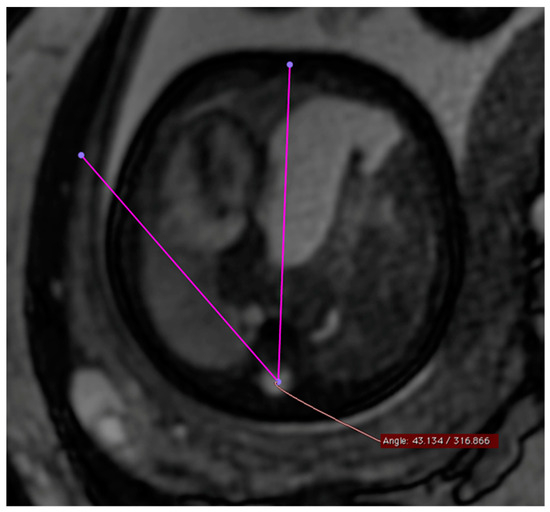

The MSA was quantified using a T2-weighted steady-state sequence (“True fast imaging with steady-state free-precision”—TRUFI) in the transverse section of the fetus in the four-chamber view. The selection of the TRUFI sequence resulted from its ability to clearly delineate the heart from the adjacent lung parenchyma. The use of the four-chamber view as a reference plane ensured easy reproducibility of the angle measurement (Figure 1). To perform the actual angle measurement, a straight line was drawn from the center of the sternum to the center of the spinal canal of the thoracic vertebral body of the same height. A second straight line was drawn from the spinal canal center of the corresponding thoracic vertebral body as a tangent at the outermost point of the pericardial side facing the diaphragmatic defect. The resulting smaller angle α between these two straight lines corresponded to the MSA.

This figure illustrates a T2 steady-state free-precision (TRUFI) sequence in the axial section plane (uniform four-chamber plane) of a fetal MRI scan in a patient with left congenital diaphragmatic hernia (CDH). In this MRI representation, the measurement of the mediastinal shift angle α is visualized as an example.